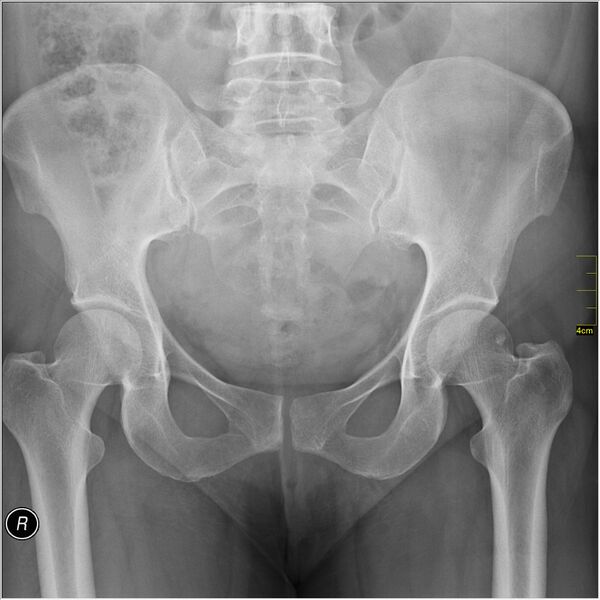

Кости таза

Основу таза образуют две тазовые кости, крестец и копчик, соединённые суставами пояса нижних конечностей в костное кольцо, внутри которого образуется полость, заключающая внутренние органы. До возраста 16—18 лет кости (подвздошная, лобковая и седалищная) соединены хрящами. Впоследствии происходит окостенение, и указанные кости срастаются между собой, образуя тазовую кость.

Парные тазовые кости спереди соединяются при помощи лобкового симфиза, а сзади прикрепляются ушковидными поверхностями к одноимённым образованиям крестца, образуя парные крестцово-подвздошные суставы. Каждая из тазовых костей в свою очередь образована тремя составляющими: подвздошной костью, седалищной костью и лобковой костью, тела которых на наружной поверхности образуют вертлужную впадину — суставную ямку для головки бедренной кости, с которой образуют тазобедренный сустав.